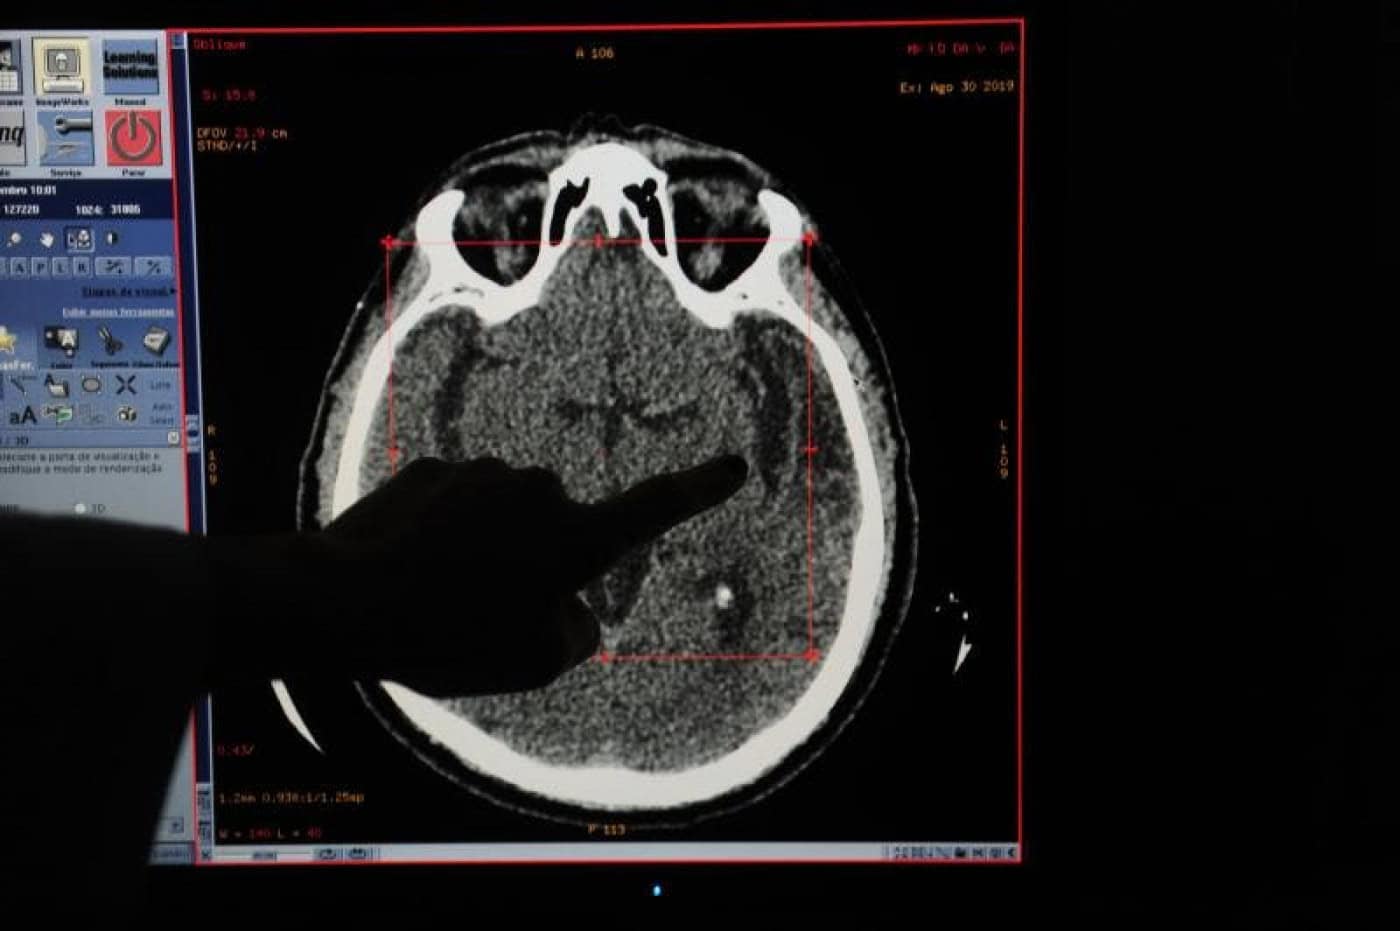

Consultas atrasadas e tratamentos a meio gás aumentam risco de AVC

Para o responsável outro dos efeitos da pandemia é a quebra de idas ao hospital em caso de AVC. “Muitos fazem-no numa fase tardia o que aumenta a gravidade da situação”, garante.